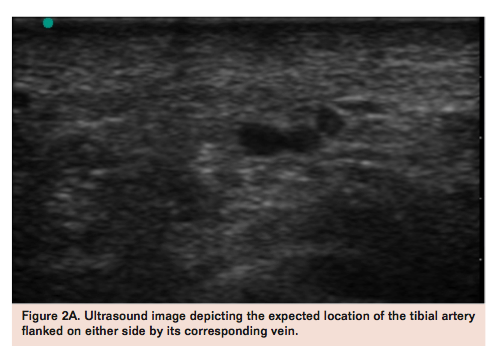

Transpedal access can be performed under direct ultrasound, fluoroscopic, and angiographic or roadmap guidance (Figure 2). A handheld duplex ultrasound can generally identify the desired pedal vessel for puncture.

It is important to recognize the vessel in both long- and short-axis views to avoid venous puncture. Compression sonography helps identify the pulsatile artery from the adjacent vein, although Doppler interrogation may be used when arterial pressure is markedly diminished to ascertain which structure represents the pedal artery. When viewed in short axis, the artery is usually flanked by the accompanying vein on both sides (Figure 2A). In general, if wire passage is free and smooth, one should inject a small amount of contrast to confirm arterial vs venous access. In a heavily calcified pedal vessel one can perform the pedal puncture under direct fluoroscopic guidance (Figure 2B).